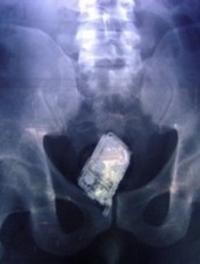

Si tu vas à rio…n’oublie pas tes 43 préservatifs !

Rio, le samedi 28 mai 2016 – Le village olympique étant un espace social propice aux rencontres de jeunes adultes en pleine possession de leurs moyens, les performances que réaliseront les sportifs qualifiés pour les jeux, en dehors des différents terrains de compétitions, sont aussi au centre des attentions [...]